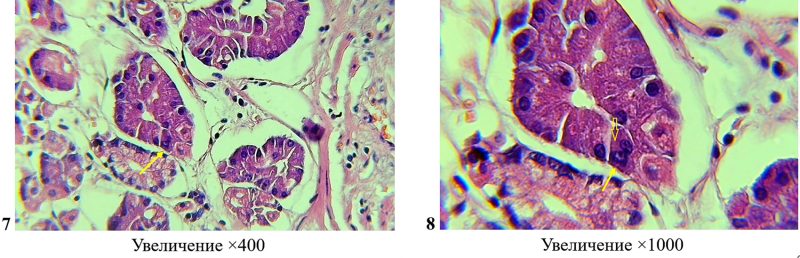

Surgical specimen of the resected body of the stomach for moderately differentiated adenocarcinoma. Photos 7-8: in the fundic glands, near the tumor tissue, there is a main cell with morphological features of a heterokaryon of hybrid origin (shown by arrows). Hematoxylin-eosin staining.